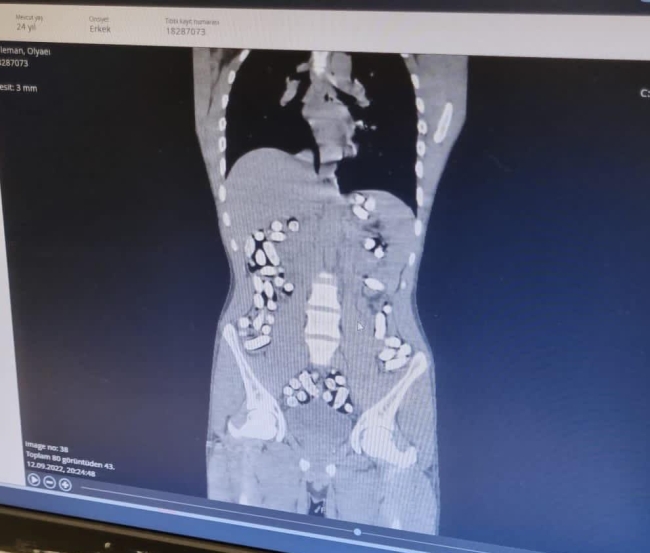

Yapılan muayene ve röntgen çekimi sonrası şüphelilerin uyuşturucuları kapsül haline getirerek yuttukları belirlendi.

Yapılan çalışmayla şüphelilerin midesindeki toplam 210 kapsül içindeki 3 kilo 192 gram Afyon sakızı ve 62 kapsül halinde 709 gram eroin çıkarıldı. Emniyetteki işlemlerinin ardından adliyeye sevk edilen 3 şüpheli 14 Eylül günü tutuklandı.

Narkotik polisi, 12 Eylül’de de aynı uygulama noktasında yaptıkları aramada İran uyruklu Mesoud T. ile Soleman O.'nun çantalarında tokluk hissi veren ve mide bağırsak temizleyici ilaç bulunmasından şüphelendi.

Hastanede röntgen filmleri çekilen şahısların 411 kapsül halinde yuttukları 2 kilo 953 gram afyon sakızı çıkarıldı. Adliyeye sevk edilen 2 şüpheli de tutuklanarak cezaevine gönderildi.